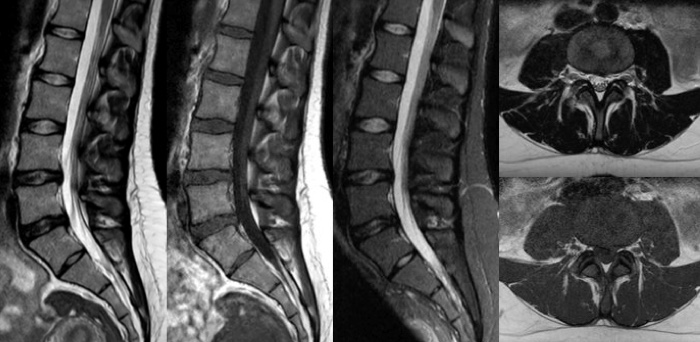

Turn images into answers – 50% faster

Put time on your side with Compressed SENSE to reduce scan time up to 50%2 with virtually equal image quality. Create exceptional MR images with 60% higher resolution for confident diagnosis.

Quality images for quality diagnoses

Our lightest Breeze coils bring extraordinary versatility to imaging challenging anatomies and the smallest joints. A large 55cm field-of-view and premium SNR add to the exceptional image quality.